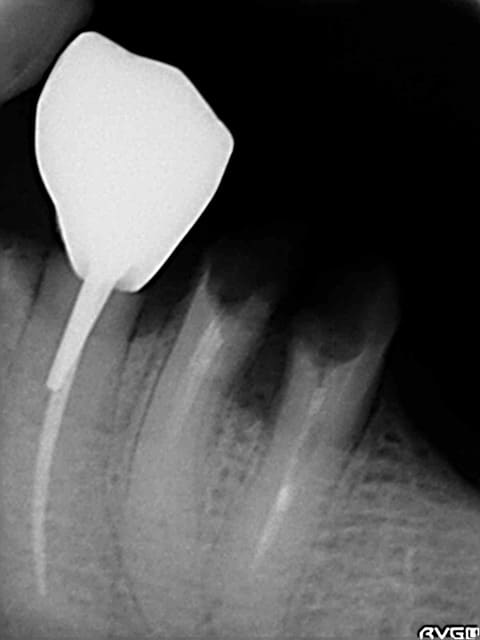

un avis implantaire pour mon premier implant au niveau d'une 36 extr faite en sept 2009

quelle longueur environ? je pensais a un 4/10mm ...

Ps extr delicate et os tres corticalisé...

derniere radio faite avec angulateur .... et en mars 2010

la crete est tres large et peu de concavite en L.

c'est juste la longeur qui m'inquiete

le cone apres extr dans l'alveole mesure 19 mm et avec la radio je mesure 18 mm : il y a peu de deformation